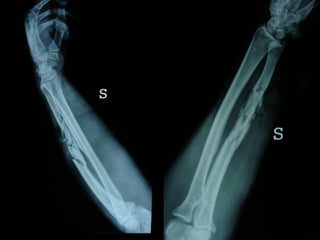

Dal Gennaio 2000 al Febbraio 2006 abbiamo trattato 167 fratture chiuse  con placca percutanea  in 164 pazienti :  27 lesioni diafisarie di gamba, 12 piloni tibiali ,  11 fratture prossimali di tibia, 36 fratture sovracondiloidee di femore, 17 fratture diafisarie di femore, 43 fratture metaepifisarie prossimali di omero, 21 diafisarie d’omero.  156 guarigioni 8 fallimenti

I buoni risultati ottenuti dipendono da 5 punti fondamentali:   una accurata riduzione percutanea della frattura  precise vie di accesso  l’utilizzo della placca che consenta il più lungo braccio di leva possibile il pretensionamento della placca  una sintesi con un ridotto numero di viti

Placche lunghe e pretensionate

Placche lunghe e pretensionate Sintesi con un ridotto numero di viti

INDICAZIONI COMUNI Fratture sovracondiloidee Fratture intercondiliodee Fratture diafisarie distali PARTICOLARI Fratture con grave osteoporosi Fratture periprotesiche

VANTAGGI CHIRURGIA MININVASIVA Mini Open Inserimento della placca sottocutaneo per scivolamento Viti percutanee Preservazione dei tessuti molli Ridotto danno vascolare Rapida ripresa funzionale

F, 68 y

LISS  NCB

NCB

Conclusioni Riduzione  anatomica Minimo trauma chirurgico Corretto equilibrio fra elasticità e stabilità Precoce mobilizzazione